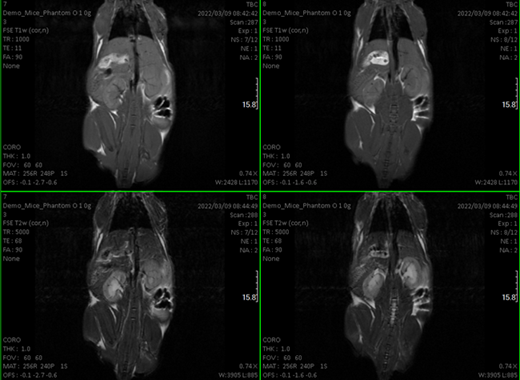

- Qualitative and quantitative studies (relaxation times T1 and T2 and even making maps) at the brain level and other organs.Cardiological sequences: diffusion, determination of blood volume…

- Oncological studies to detect and locate tumors and volume calculation.